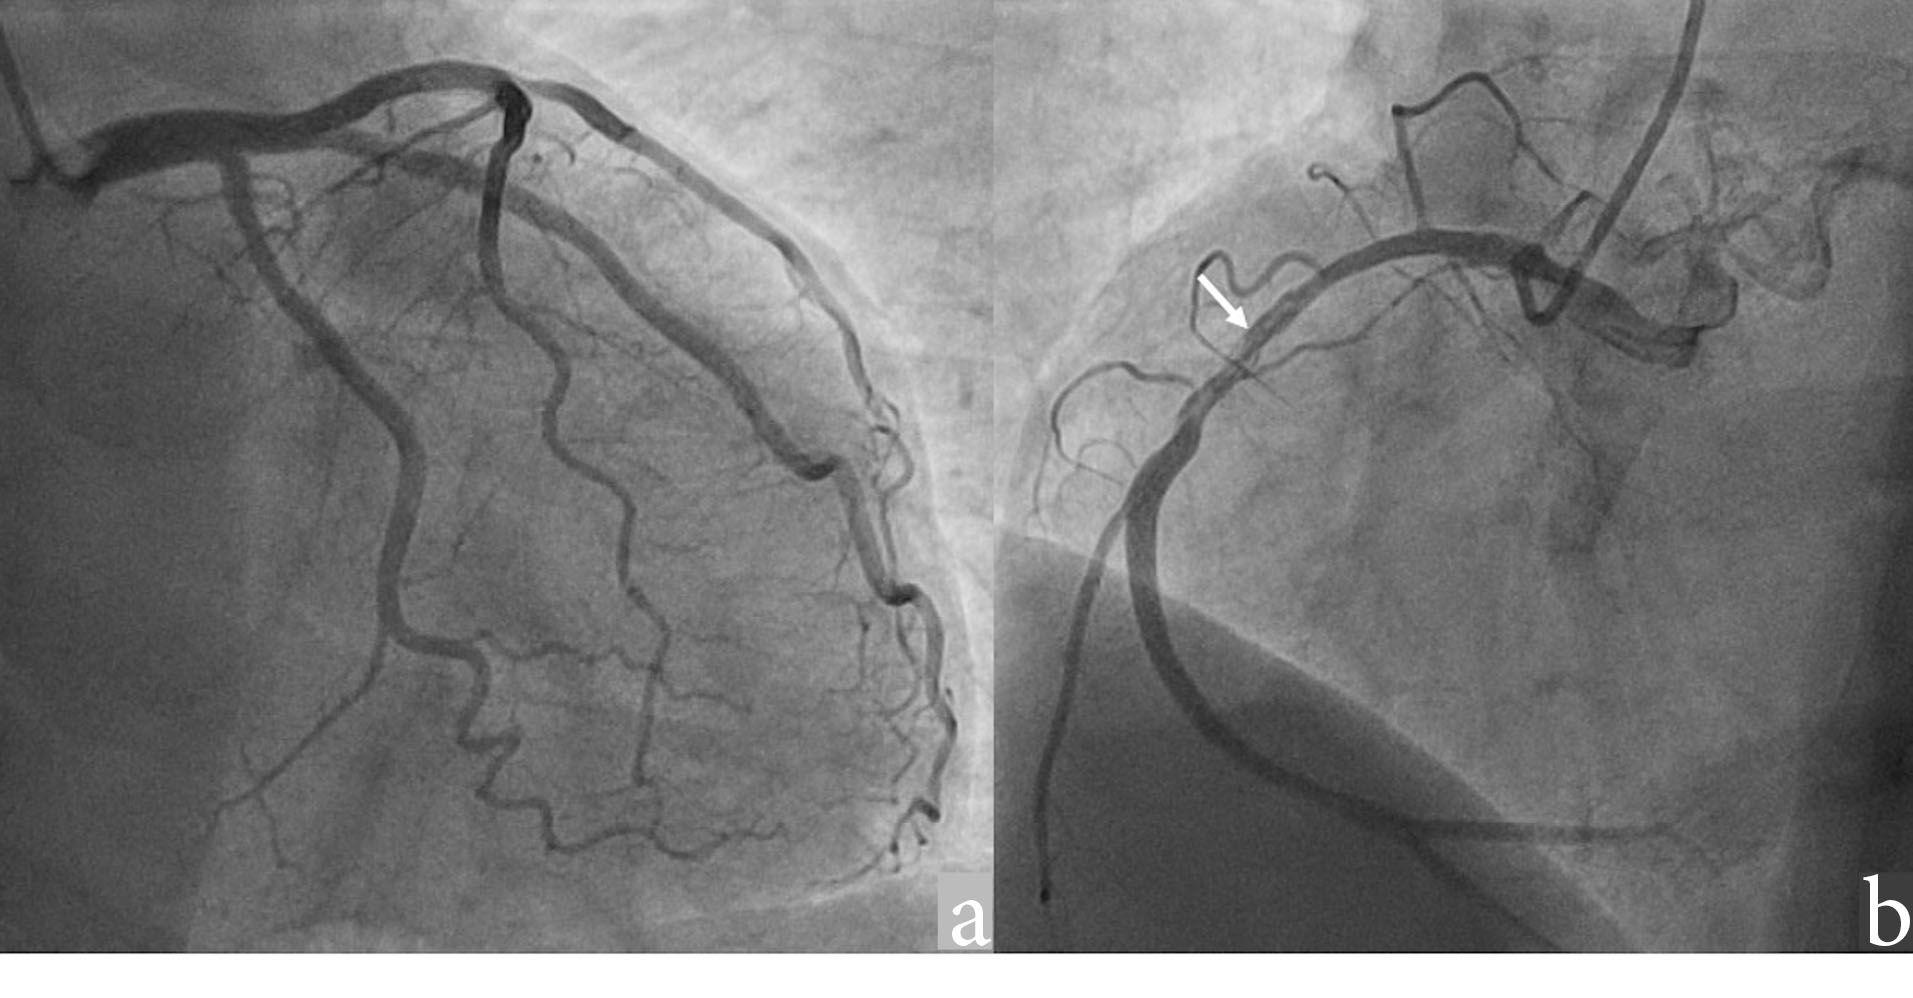

The patient had no history of hypertension, diabetes, smoking, or dyslipidemia. He denied any history of angina or syncope. On examination, the patient was having tachycardia and a blood pressure of 80/50 mm Hg with diaphoresis. During the episode of tachycardia ECG revealed monomorphic VT (right bundle branch block morphology with superior axis) (as shown in ). Sinus rhythm was immediately achieved by direct current cardioversion. Electrocardiogram (ECG) during sinus rhythm showed q waves in inferior leads with T inversion and QTc interval of 420 ms (as shown in ) suggestive of evolved inferior wall MI. Blood investigations including complete blood count, electrolytes including potassium, calcium magnesium, liver and renal function tests, and the lipid profile were within normal limits. Troponin T was elevated at 4.3 ng/mL. CD4 cell count of the patient was 987/mm3. Echocardiography of the patient showed hypokinesis in right coronary artery (RCA) territory with an EF of 50 % (as shown in , Supplementry File 1, Video S1). He was treated with amiodarone infusion, dual antiplatelets (aspirin and clopidogrel), atorvastatin, metoprolol and low molecular weight heparin. The patient underwent coronary angiography which revealed spontaneous coronary artery dissection in mid RCA (as shown in , Supplementry File 2, Video S2). Rest of the coronary vessels were normal (Supplementry File 3, Video S3). In view of lack of flow limiting stenosis and TIMI III flow, revascularization was not done. For secondary prevention, implantable cardiac defibrillator has been advised for the patient, but the patient has refused the same due to financial reasons. The patient developed no further episodes of VT during hospital admission and on follow up after a month.

jcvtr-14-71-g004

Figure 4. Angiogram images showing (a) Normal left coronary artery (b) Spontaneous coronary artery dissection in the mid RCA